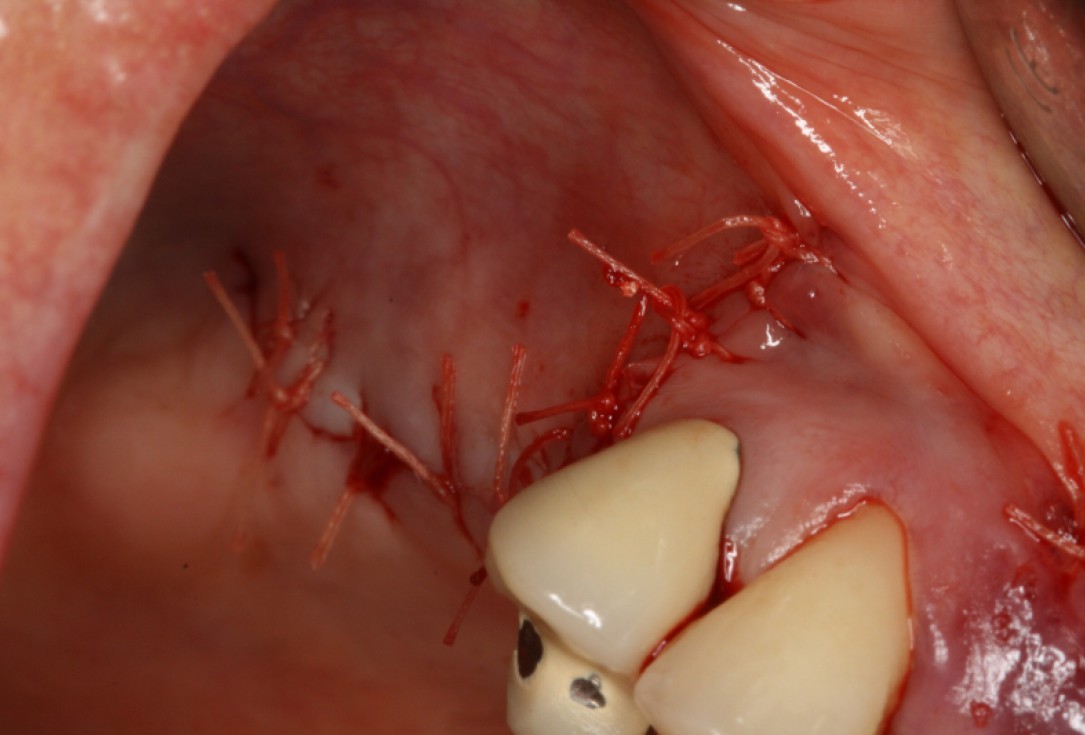

10/20 - wound closureGBR with maxresorb® & Jason® membrane - Prof. Dr. Dr. D. Rothamel

-